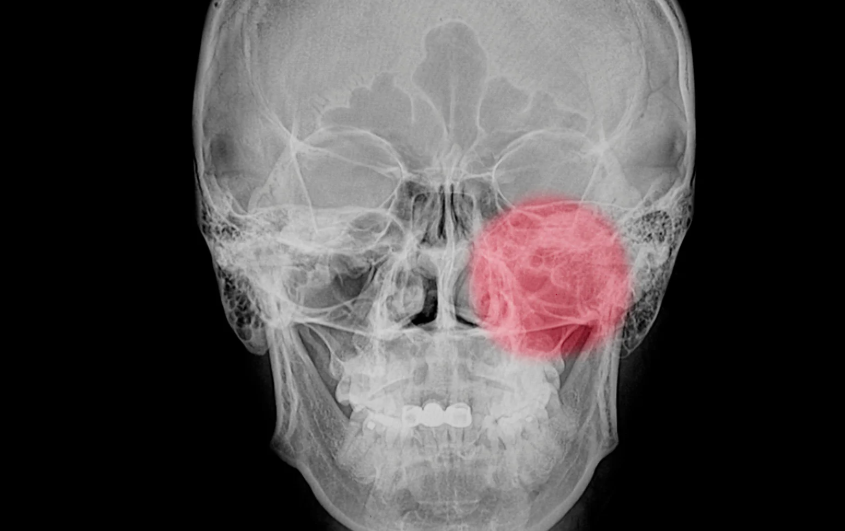

축농증의 가장 대표적인 증상은 지속적인 코막힘과 두통입니다. 평소보다 코가 꽉 막힌 듯 답답하고, 코를 풀어도 시원하지 않으며, 머리나 얼굴 부위 특히 눈 아래쪽과 이마 부근이 무겁고 아픈 느낌이 듭니다. 이와 함께 누런 콧물이 흐르거나, 후비루(콧물이 목 뒤로 넘어가는 현상)가 지속된다면 축농증을 의심해볼 수 있습니다. 이 외에도 집중력 저하, 입냄새, 후각 감소, 심한 경우에는 눈 주위 붓기까지 동반될 수 있습니다. 축농증은 단순한 감기와 증상이 비슷하지만, 감기는 보통 1주일 안에 호전되는 반면, 축농증은 수주에서 수개월 이상 증상이 지속됩니다. 따라서 ‘감기가 너무 오래 간다’고 느낀다면 꼭 이비인후과 진료를 받아보는 것이 좋습니다. 2024년 현재에는 스마트폰 앱을 통한 증상 기록 관리나 자가 진단 툴도 제공되고 있어, 초기에 자신의 증상을 체크하고 병원을 찾는 데 큰 도움이 됩니다.

축농증의 발생 원인은 다양하지만, 그중 가장 흔한 원인은 알레르기 반응과 면역력 저하입니다. 알레르기성 비염이 있는 사람은 부비동 점막이 자주 붓고 염증이 반복되어 축농증으로 발전할 가능성이 높습니다. 또한 면역력이 떨어져 있는 상태에서는 감염이 쉽게 발생하며, 바이러스나 세균이 부비동에 침투해 고름이 생기고 염증이 장기화될 수 있습니다. 코 구조의 이상도 중요한 원인 중 하나입니다. 비중격이 휘어져 있거나 콧속 용종(물혹)이 있는 경우에도 코 안의 배농이 원활하지 않아 축농증이 생길 수 있습니다. 이러한 해부학적 문제는 약물치료만으로는 완치가 어렵기 때문에 정밀한 진단과 경우에 따라 수술이 필요할 수 있습니다. 2024년 의료 트렌드에 따르면, 유전자 기반 면역반응 분석을 통해 개인 맞춤형 알레르기 치료를 시도하는 병원이 늘고 있으며, 예방 중심의 접근이 점점 강화되고 있는 추세입니다.